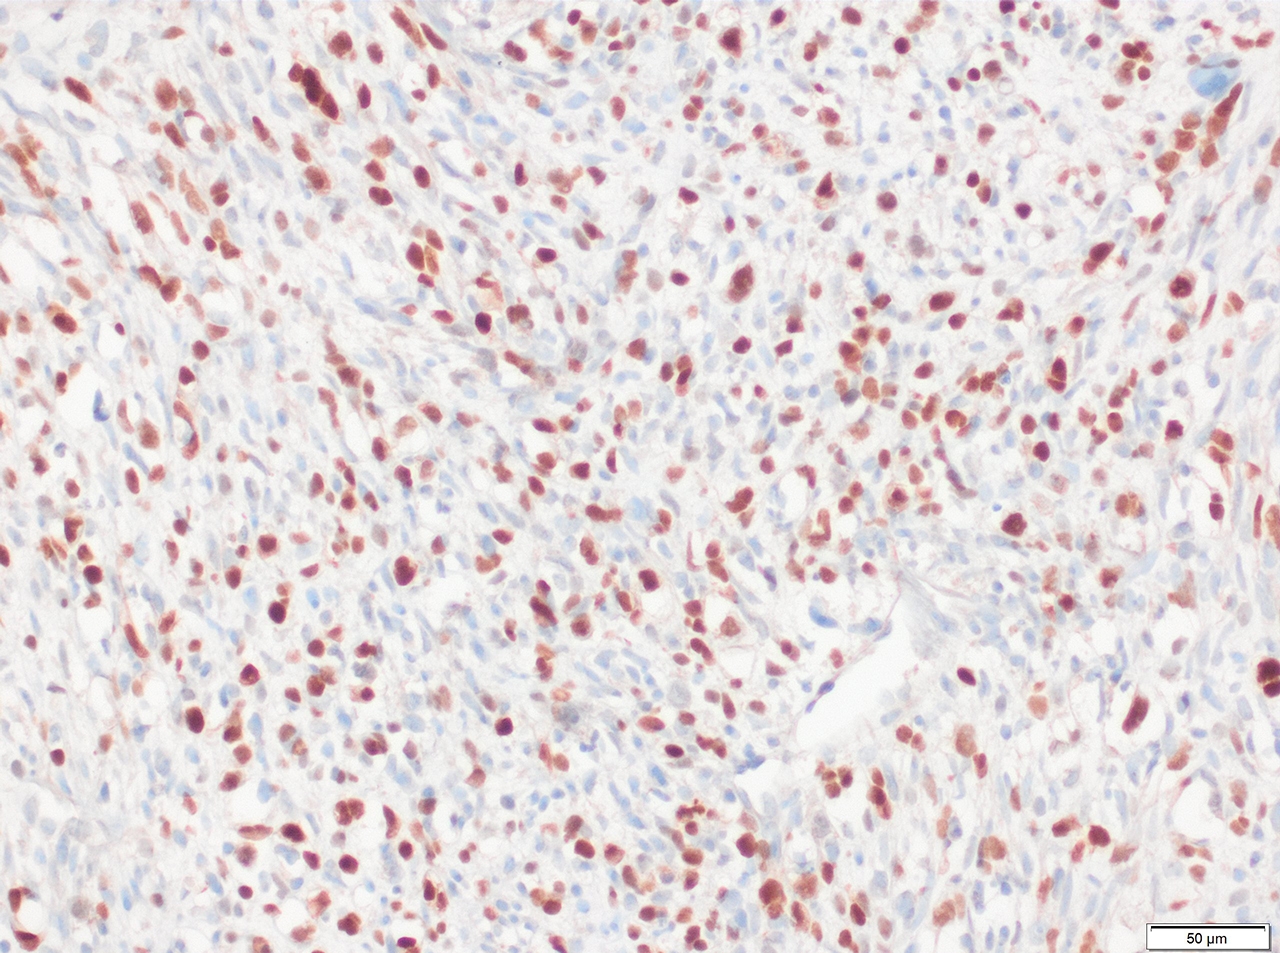

Positive stains

- Desmin, MyoD1 or myogenin are critical to document (Pathol Oncol Res 2008;14:233)

- Without myogenic differentiation (MyoD1 or myogenin), it is very difficult to diagnose embryonal rhabdomyosarcoma

- These stains will be less diffuse than in alveolar rhabdomyosarcoma and can be extremely focal

- Comment: Histologic sections of this left chest wall excision demonstrate a spindle cell sarcoma comprised of hyperchromatic cells arranged into disorganized intersecting fascicles. No evidence of anaplastic features is identified. Immunohistochemical staining shows diffuse positivity for desmin, with scattered cells positive for myogenin and MyoD1. These findings are compatible with embryonal rhabdomyosarcoma.